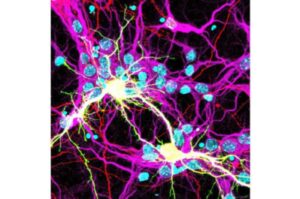

SARS-CoV-2 può causare la fusione delle cellule cerebrali

SARS-CoV-2-Immagine: neuroni fusi (gialli) che esprimono il fusogeno Spike S dal virus SARS-CoV-2 e dal recettore umano hACE2. Credito: gli autori-…